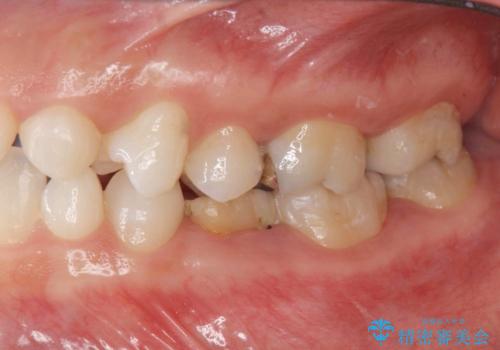

- 大人になっても残存していた乳歯がグラグラし、痛くて噛めない 抜いて欲しいとの希望で来院されました。

歯根が吸収し残すことのできない乳歯を抜去後、隣の歯を削らずに済むインプラント治療で咬合機能の回復を計画します。

乳歯の抜去後、インプラントを用いてしっかりと咬合機能を回復することができました。